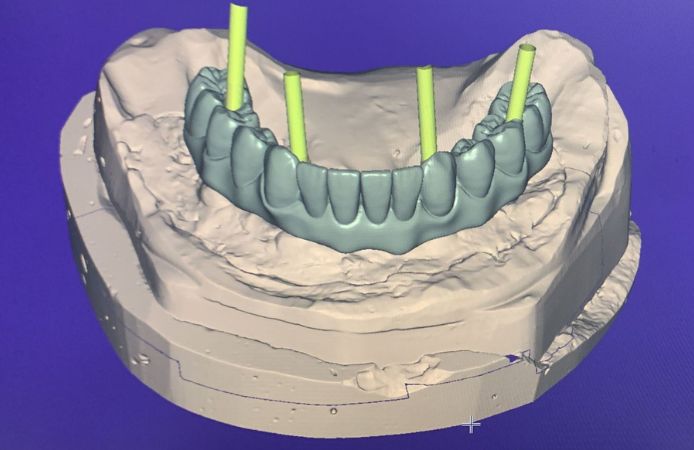

Figure 1.

Figure 2.

Figure 3.

Figure 4.